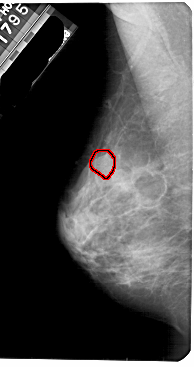

A_1888_1.LEFT_MLO

LEFT_MLO LINES 5491 PIXELS_PER_LINE 2896 BITS_PER_PIXEL 12 RESOLUTION 43.5 OVERLAY

FILE: A_1888_1.LEFT_MLO.OVERLAY

TOTAL_ABNORMALITIES 1

ABNORMALITY 1

LESION_TYPE CALCIFICATION TYPE PUNCTATE DISTRIBUTION CLUSTERED

ASSESSMENT 4

SUBTLETY 2

PATHOLOGY BENIGN

TOTAL_OUTLINES 1

BOUNDARY